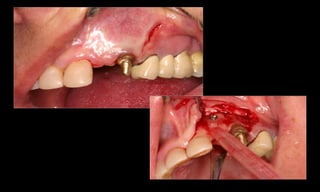

10-10-2005

Novembro de 2005

24-01-2006

Cone Morse